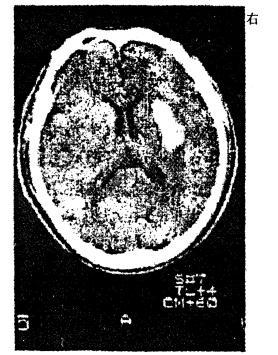

问题 男性,56岁。高血压患者。旅游登山中突然左侧 肢体发麻、乏力。急送医院,摄头颅CT片如图 CT影像中描述病灶呈 A.高信号区 B.低信号区 C.低密度区 D.高密度区 E.不等密度区

答案 D